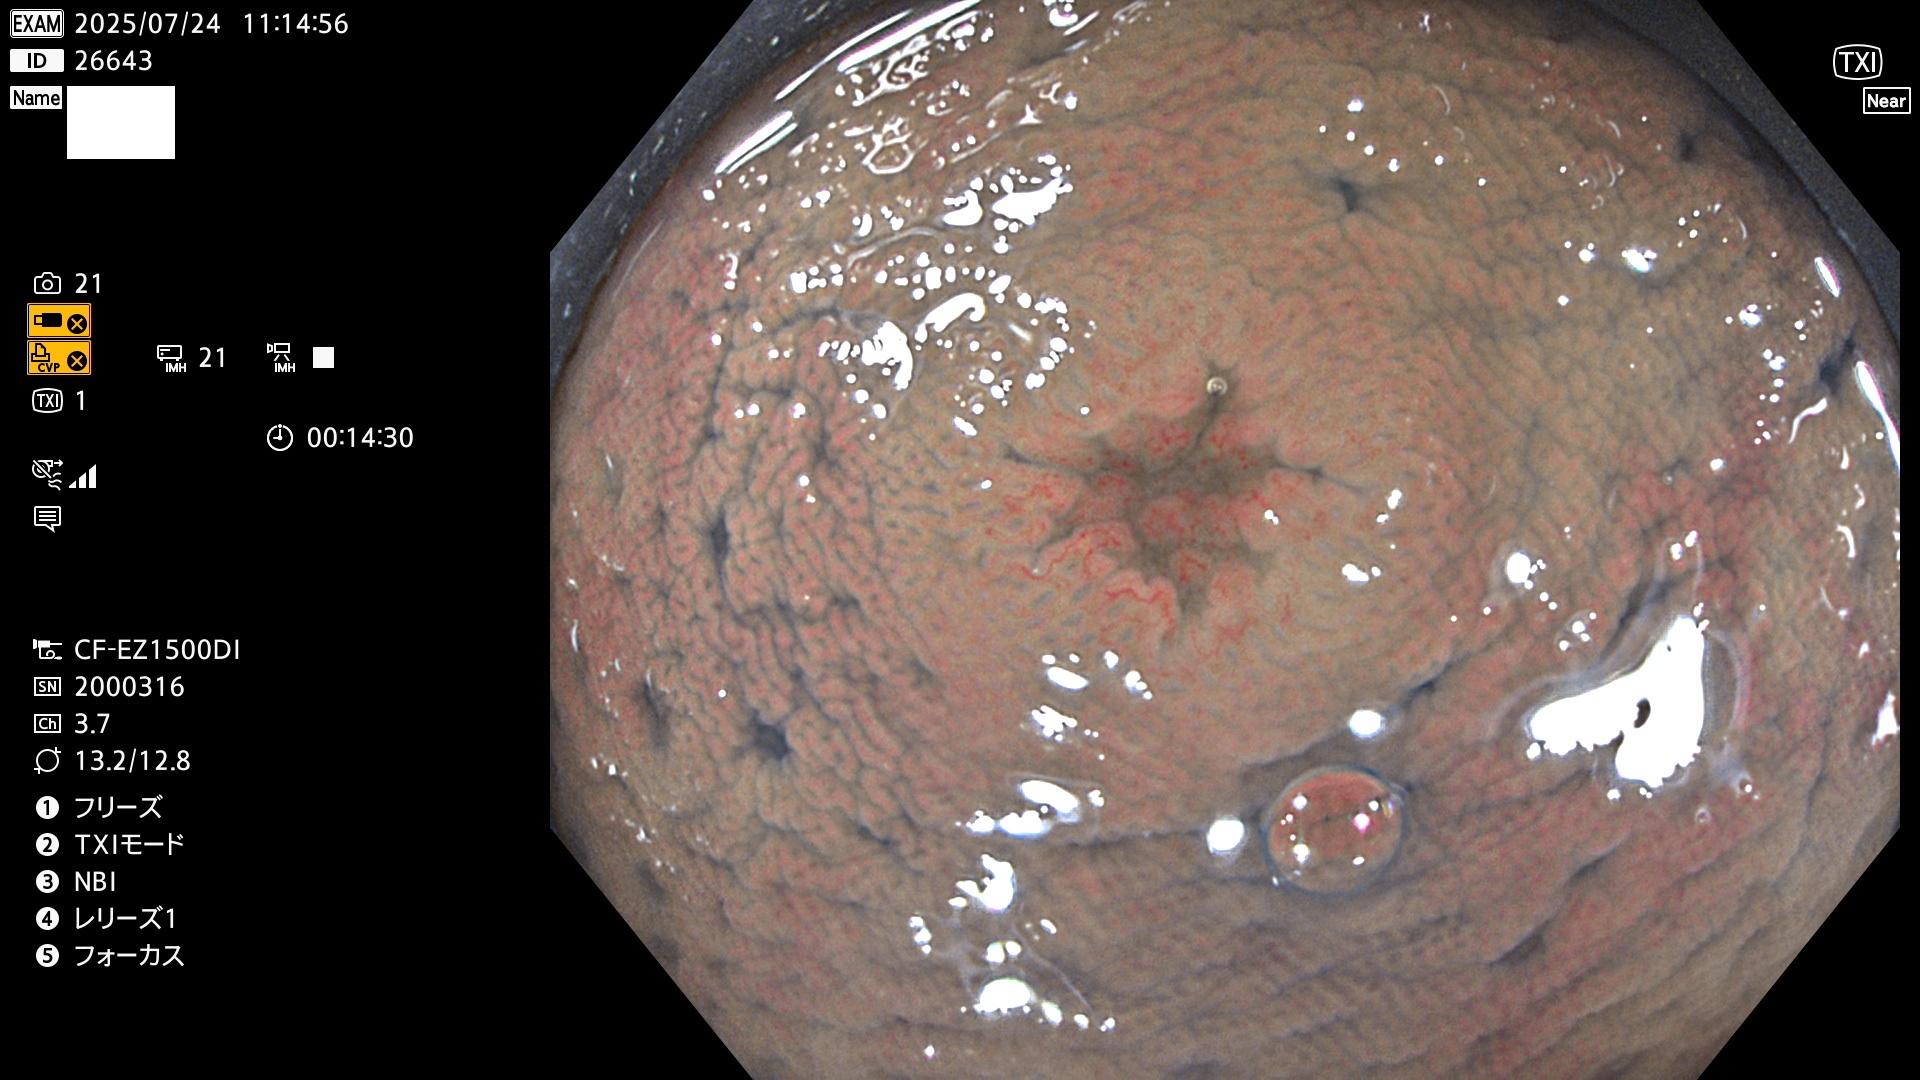

完全に平坦な物をUb、陥凹している物をUcと呼びます。Ubは認識が困難で、Ucはびらん(炎症)と紛らわしいために見落とされやすく、「内視鏡後・大腸癌」の原因になります。

専門的)Uc=De Novo癌? 内視鏡の解像度が低かった時代、このような説もありました。しかし今日の高精度内視鏡では良性の微小なUc型腺腫(APC遺伝子異常の腺腫)が日常的に見つかります。Ucこそが多段階発癌(Adenoma-Carcinoma Sequence)のMain Routeです。

2025年7月24日〜7月27日の4日間(40件)15個 (Uc_ADR=15個/40人=38%)